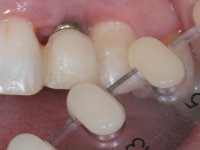

O tratamento iniciou-se com a re -preparação do coto do espigão falso coto fundido, com o objetivo de colocar as linhas de acabamento cervical com uma localização intra-sulcular e simultaneamente confecionar uma coroa provisória adaptada. Com um tratamento ortodôntico muito simples, fechou-se o diastema entre os incisivos centrais superiores e estabilizou-se esta posição com um arame colocado na superfície palatina dos centrais, funcionando como contenção. Posteriormente procurou-se fazer uma tração ortodôntica lenta do dente 2.2 com o intuito de diminuir, ainda que muito ligeiramente a perda óssea vertical nessa zona. Finalizada a tração, foi feita a extração do dente 2.2 e a zona foi reabilitada provisoriamente com uma coroa de resina composta colada aos dentes adjacentes. Foi colocado um implante dentário na zona do dente 2.2 sendo novamente colada a coroa provisória em resina, reabilitando provisoriamente a paciente durante o período de osseointegração. No dente 1.3 foi feita uma gengivectomia com bisturi elétrico, com a intenção de subir o nível cervical do 1.3 conseguindo uma maior harmonia com o dente 2.3. Estabilizados os tecidos moles, foi feita uma impressão com a técnica de moldeira aberta, utilizando silicones de adição de consistência “putty” e “light”. A recolha da cor, tanto da componente dentária como dos tecidos moles foi feita pelo ceramista no consultório.  No laboratório as impressões foram passadas a gesso e deram origem a modelos de trabalho que foram devidamente analisados. Foi decidido confecionar um “abutment” metalo-cerâmico aparafusado sobre o implante. Este “abutment” foi fundido com uma liga nobre e posteriormente revestido a cerâmica coronária e gengival. Dada a inclinação do implante o aparafusamento condicionou de forma inevitável a saída do orifício do parafuso pela superfície vestibular. No sentido de esconder esta situação, o desenho do “abutment” já foi idealizado com a intenção de acomodar na superfície vestibular a colagem de uma faceta feldspática. Este “abutment” foi provado em boca e foram feitos ajustes no componente cerâmico gengival. A sua adaptação aos tecidos moles foi feita tanto de forma subtrativa, com broca, como de forma aditiva, acrescentando resina composta de tonalidade gengival. Este acrescento de resina seria orientador do ceramista na colocação final da cerâmica de tonalidade gengival. A coroa que reabilitaria o dente 1.3 foi cimentada nesta consulta de prova com cimento de ionómero de vidro reforçado com resina composta. Finalizado o trabalho em laboratório da faceta sobre o 1.2 e o “abutment” e a faceta para o implante este foi colado em boca, após a colocação do isolamento absoluto. O trabalho satisfez plenamente a paciente. Durante oito anos a paciente foi seguida regularmente, mostrando-se agradada com o tratamento efetuado, no entanto começou a mostrar interesse em intervir esteticamente nos incisivos centrais superiores. Decidida a segunda fase da nossa intervenção, foi feita a preparação dentária dos dentes 1.1 e 2.1 para a colocação de duas facetas feldspáticas. Particular cuidado foi tido na preparação inter-proximal distal junto ao “abutment” do implante. Foi preciso avaliar muito pormenorizadamente o eixo de inserção da faceta em relação ao “abutment”. As facetas feldspáticas foram confecionadas em laboratório e posteriormente coladas em boca após a colocação de isolamento absoluto. Um ano após, iniciamos a nossa terceira fase de tratamento, após a faceta colada no dente 2.1 ter fraturado. A preparação dentária foi feita sobre a faceta colada, procurando estender mais para palatino o interface inter-proximal distal. O objetivo seria passar para mais palatino do ponto de contacto o interface faceta-dente. O preparo dentário do dente 1.2 também foi muito reduzido, limitando-se a criar um eixo de inserção. Após confecionadas a coroa total e a faceta em laboratório foram coladas em boca. Primeiro foi colada a coroa utilizando-se um isolamento relativo com teflon, posteriormente foi colada a faceta após a colocação do isolamento absoluto. Na coroa utilizei este tipo de isolamento para evitar a utilização de grampos. Seria difícil de aplicar pela forma e dimensão do dente e agressivo para os tecidos moles. Após a colagem foi avaliada a integração oclusal do trabalho.